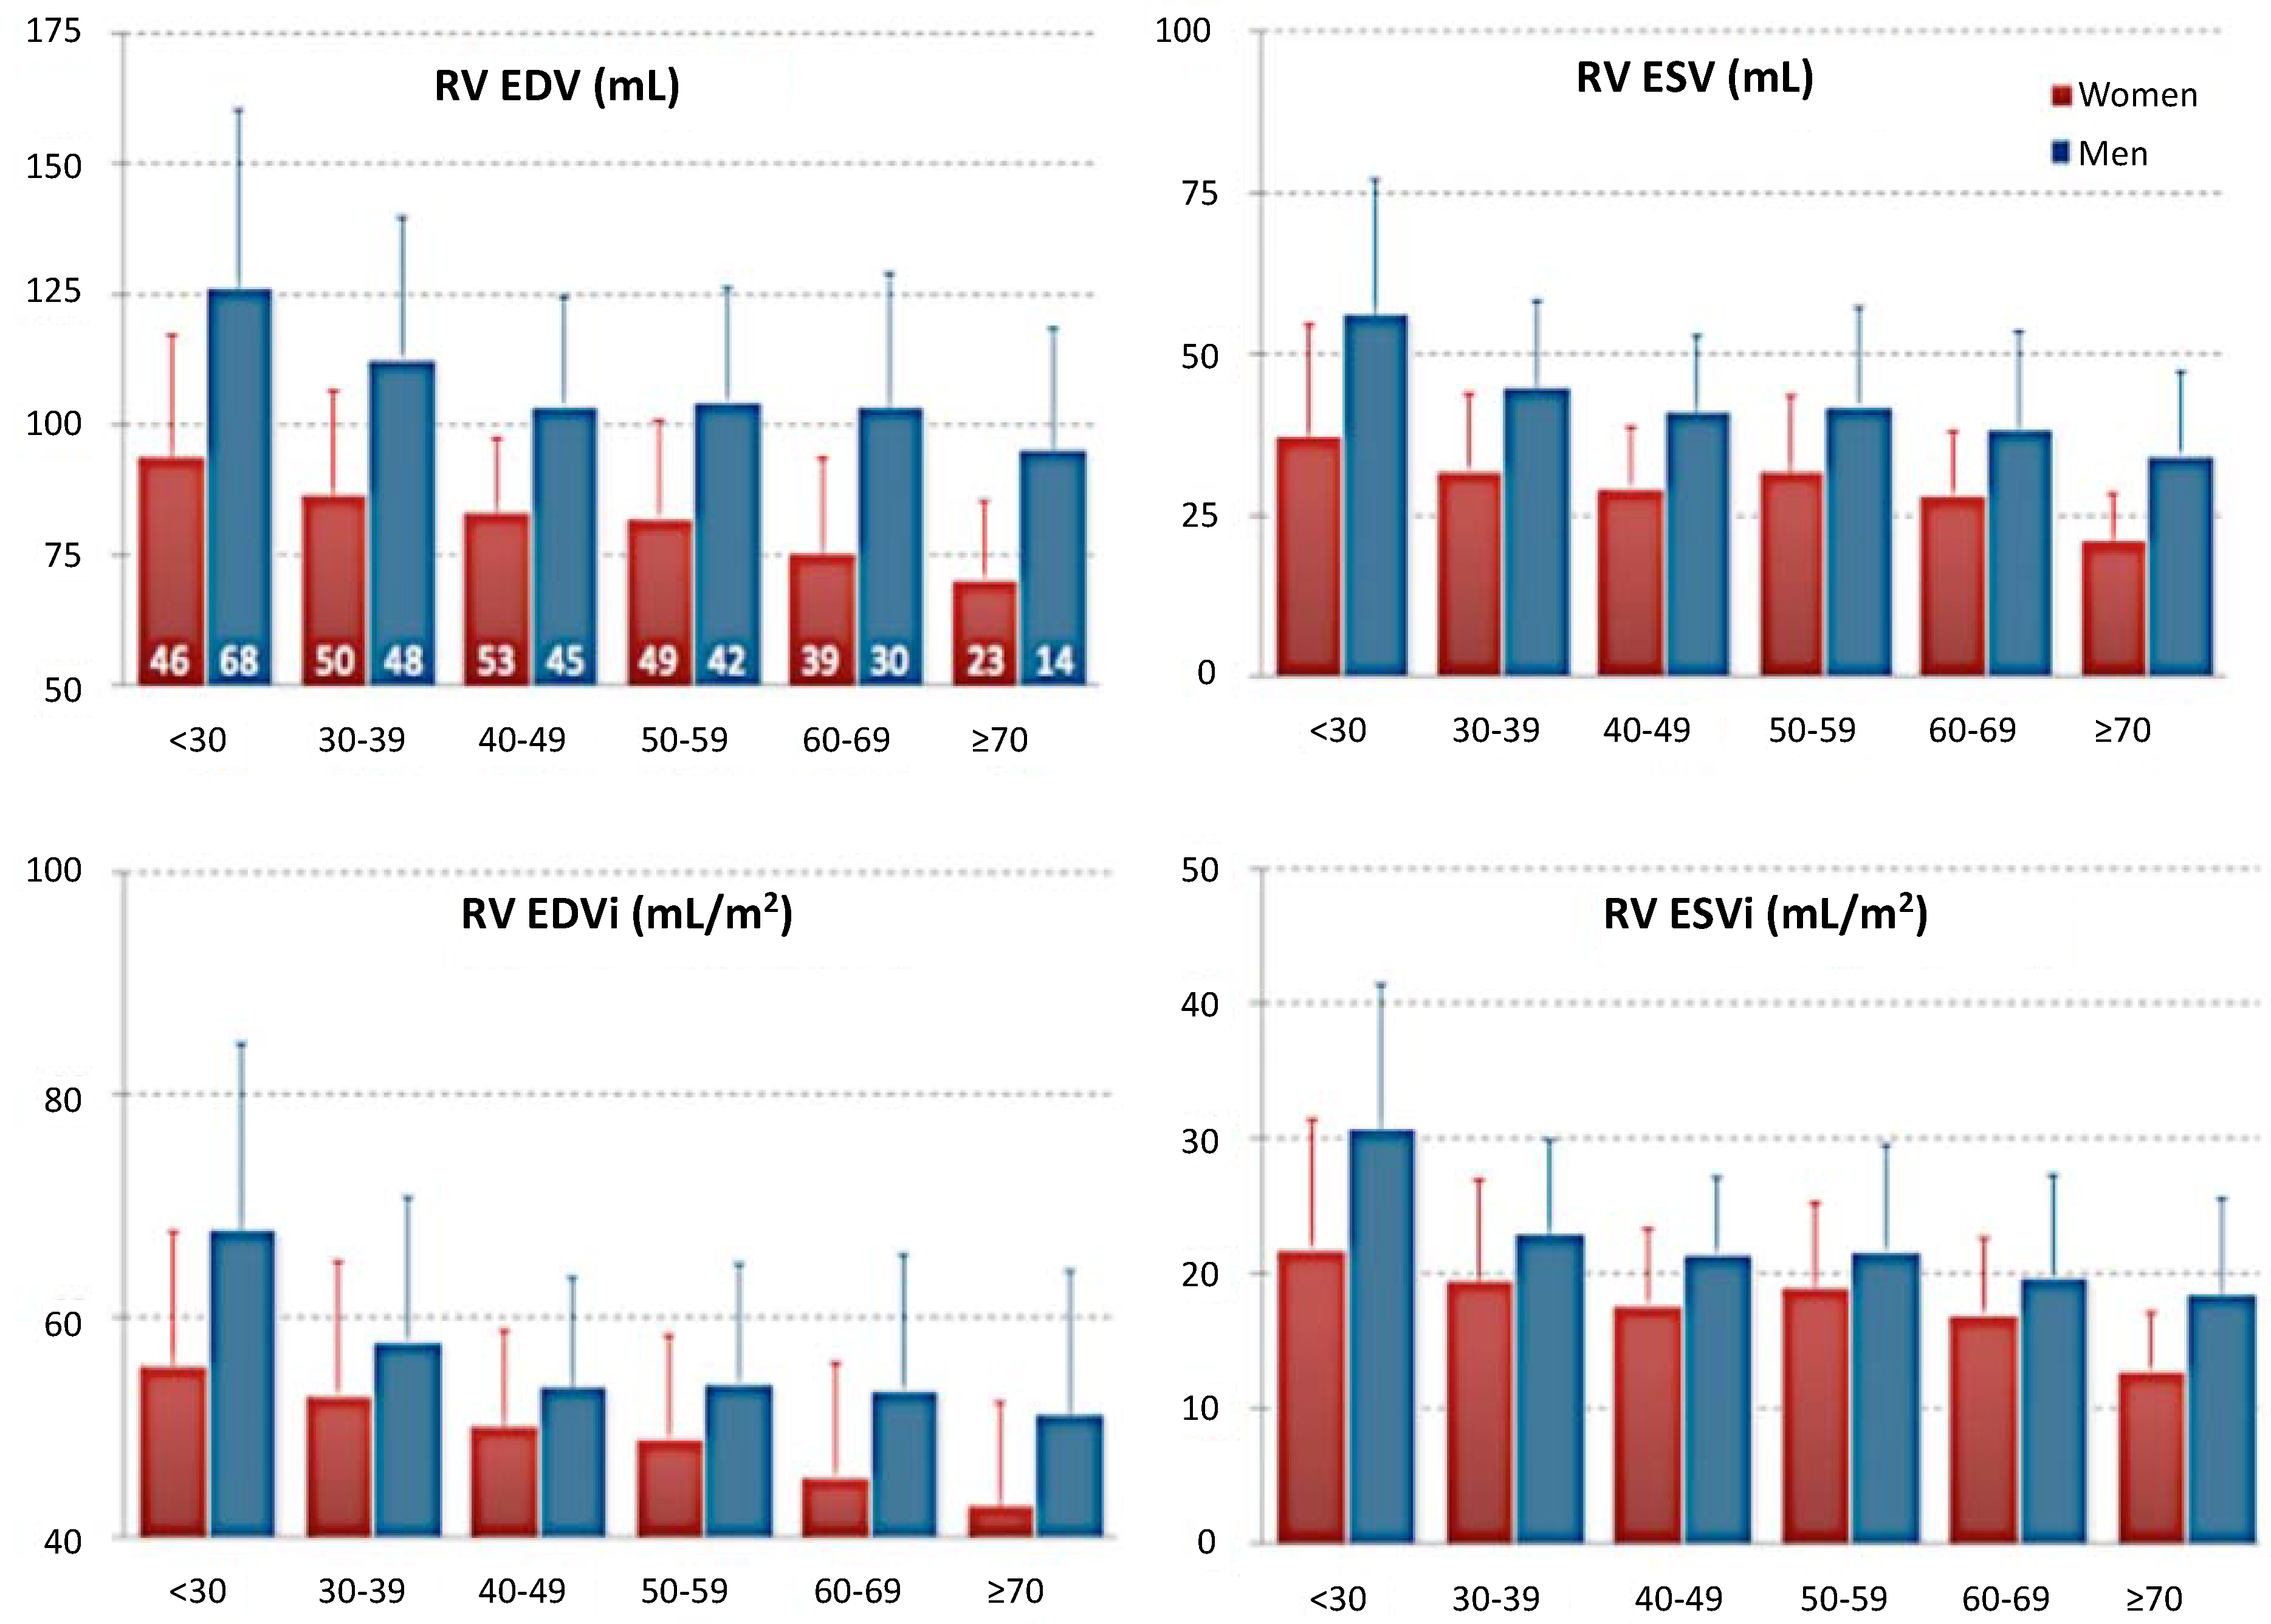

- Maffesanti, F.; Muraru, D.; Esposito, R.; Gripari, P.; Ermacora, D.; Santoro, C.; Tamborini, G.; Galderisi, M.; Pepi, M.; Badano, L.P. Age-, body size-, and sex-specific reference values for right ventricular volumes and ejection fraction by three-dimensional echocardiography. Circ. Cardiovasc. Imag 2013, 6, 700–710. [Google Scholar] [CrossRef]

- Maceira, A.; Prasad, S.; Khan, M.; Pennell, D. Reference right ventricular systolic and diastolic function normalized to age, gender and body surface area from steady-state free precession cardiovascular magnetic resonance. Eur. Heart J. 2006, 27, 2879–2888. [Google Scholar] [CrossRef] [PubMed]